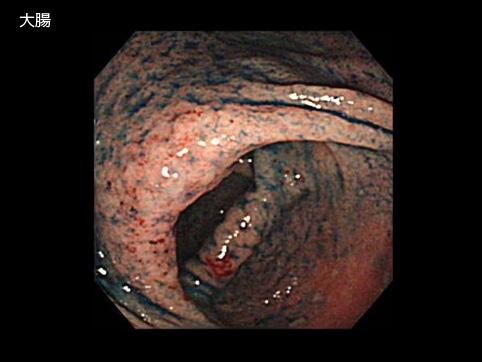

症例提示(所在地,施設名等): 佐賀県・ 佐賀大学医学部放射線科 (水口昌伸先生からの提供症例)

疾患(病理主体)の分類炎症性・潰瘍性疾患/潰瘍性大腸炎

部位(臓器別)大腸/2区域以上の大腸にまたがるもの

検査方法内視鏡

病変の最大径(ミリ)40以上